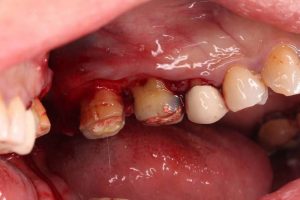

2 翻瓣:醫生會沿著牙齦邊緣劃開一條細長的口,將牙齦從牙齒上分離,露出牙根表面以利清理。

3 清理:醫生會用特殊工具清除牙根表面的細菌、組織和結石,消除感染源。

4 修復:如果您的牙骨已經受到損害,醫生會移除腐骨,用人工材料或自身組織填補缺損部位,增加牙齒的支撐力。

5 縫合:醫生會將牙齦重新貼合到牙齒上,並用細小的縫合針將切口處密封,防止出血和感染。